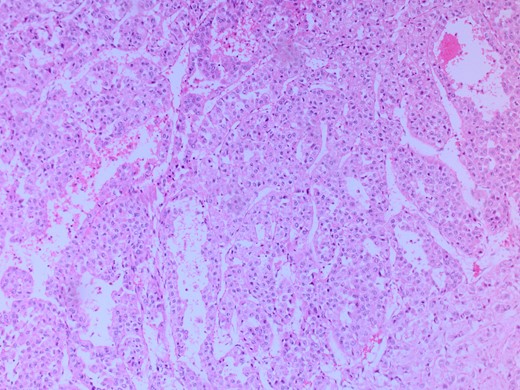

She had a CT chest to complete the staging workup, which was negative for metastasis. Eventually, she had a pancreaticoduodenectomy (Whipple procedure) with smooth postoperative recovery. The patient was discharged home on postoperative Day 7. The final histopathology came as moderately differentiated adenocarcinoma, pancreaticobiliary type with focal squamous differentiation (5%), invasion into the muscularis propria of the duodenum, and positive lymphovascular invasion with 1/12 LN positive for tumor deposits (Figs 3–6). All surgical margins were tumor-free. After a multidisciplinary meeting, the decision was made with proceed for adjuvant chemotherapy. Currently, she is on adjuvant chemotherapy, which she is tolerating well. Follow-up CT CAP at 3- and 6-month intervals postoperatively showed no evidence of recurrence or distant metastasis.

Microscopic image with H&E staining shows a tumor interface with normal liver parenchyma.